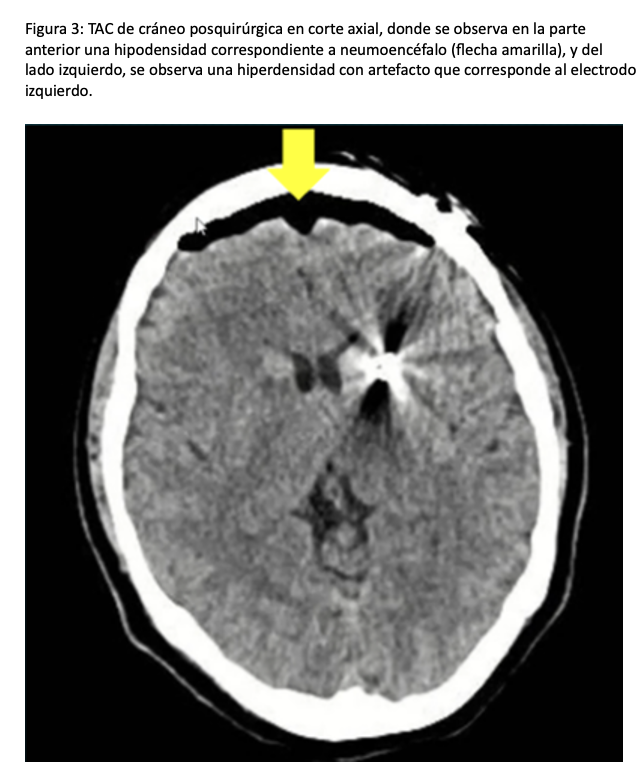

La paciente egresó a la unidad de terapia intensiva, previa realización de nuevo estudio de tomografía, donde se evidenció la presencia de neumoencéfalo (Figura 3). Durante su estancia en la unidad de terapia intensiva, se mantuvo en vigilancia durante 24 horas, no presentó nuevas crisis epilépticas. Posteriormente, se dio de alta a su domicilio y se reprogramó para completar la cirugía, en la cual no se reportaron nuevas complicaciones.

La incidencia de crisis epilépticas durante la colocación de DBS es 0.4-4 %, la mayoría suele ser de nueva aparición y hasta el 40 % se asocian con anormalidades en el estudio de imagen (neumoencéfalo, edema o hemorragia). Atchley y cols, evaluaron la incidencia y factores de riesgo asociados a crisis epilépticas durante colocación de DBS, encontrando una incidencia de 3.4 % en su estudio retrospectivo. Así mismo encontraron como un factor de riesgo para presentar crisis epilépticas pertenecer a la población joven, debido probablemente a una menor tolerancia al neumoencéfalo, edema o hemorragia durante la colocación de los electrodos. Este factor de riesgo estuvo presente en la paciente, ya que, al ser una mujer en la quinta década de la vida, existía una mayor probabilidad de irritación cortical secundaria al neumoencéfalo. Este último se genera por la apertura y cierre de la duramadre durante la colocación del electrodo a través del trépano. Dichos cambios en el contenido intracraneal suelen ser menos tolerados en pacientes jóvenes que en adultos mayores, quienes generalmente presentan cierto grado de atrofia cerebral y, por lo tanto, una mayor capacidad para compensar estas alteraciones (5).